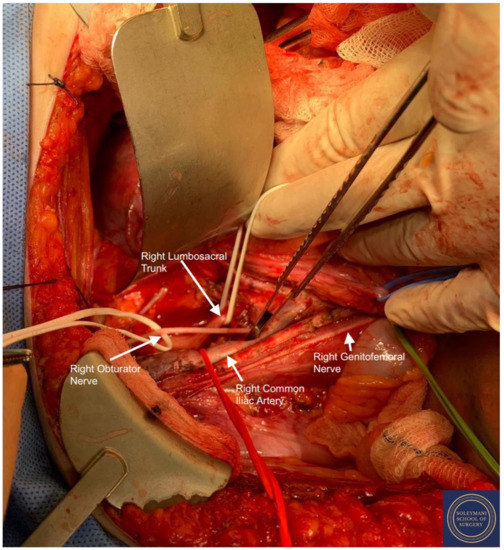

Approach to Radical Hysterectomy for Cervical Cancer in Pregnancy: Surgical Pathway and Ethical Considerations

by Rocco Guerrisi, Sarah Louise Smyth, Lamiese Ismail, Amanda Horne, Federico Ferrari and Hooman Soleymani majd

J. Clin. Med. 2022, 11(24), 7352; https://doi.org/10.3390/jcm11247352 - 10 Dec 2022

Introduction. Cervical cancer is currently the fourth most common cancer in women and in the poorest countries this neoplasia still represents a widespread and potentially lethal disease. We present a rare case of cervical cancer in pregnancy, analyzing the historical changes behind the procedure of radical hysterectomy for cervical cancer and discussing variations in surgical techniques and anatomical definitions that have since been proposed. Results. We present the case of a 33-year-old patient who attended with vaginal bleeding in the second trimester of pregnancy. Examination revealed an abnormal looking cervix, with investigations concluding stage IIb squamous cell carcinoma. Following extensive discussion regarding management options, the patient went on to have a peripartum foetocidal type III nerve sparing radical Wertheim hysterectomy at 18 weeks gestation with conservation and transposition of the ovaries above the level of the pelvic brim. The patient recovered well without significant morbidity and received further input from fertility and psychological medical teams in addition to adjuvant treatment within the department of clinical oncology. Discussion. This case represents several elements of great interest and learning. Notably, we highlight this both due to the surgical challenges that a gravid uterus presents in the execution of a radical hysterectomy; and regarding the compassionate care demonstrated by the team - not only in supporting the patient and her partner in a period of profound turmoil in terms of the management of their cancer diagnosis and unborn child, but also regarding the uncertainty in consideration of the oncological and fertility related outcomes. Conclusion. This manuscript adds to the growing literature on the appropriate use of radical surgery for cervical cancer, more specifically during pregnancy and in consideration of such ethical dilemma, where management guidelines do not exist to aid clinicians further in their provision of treatment. Full article